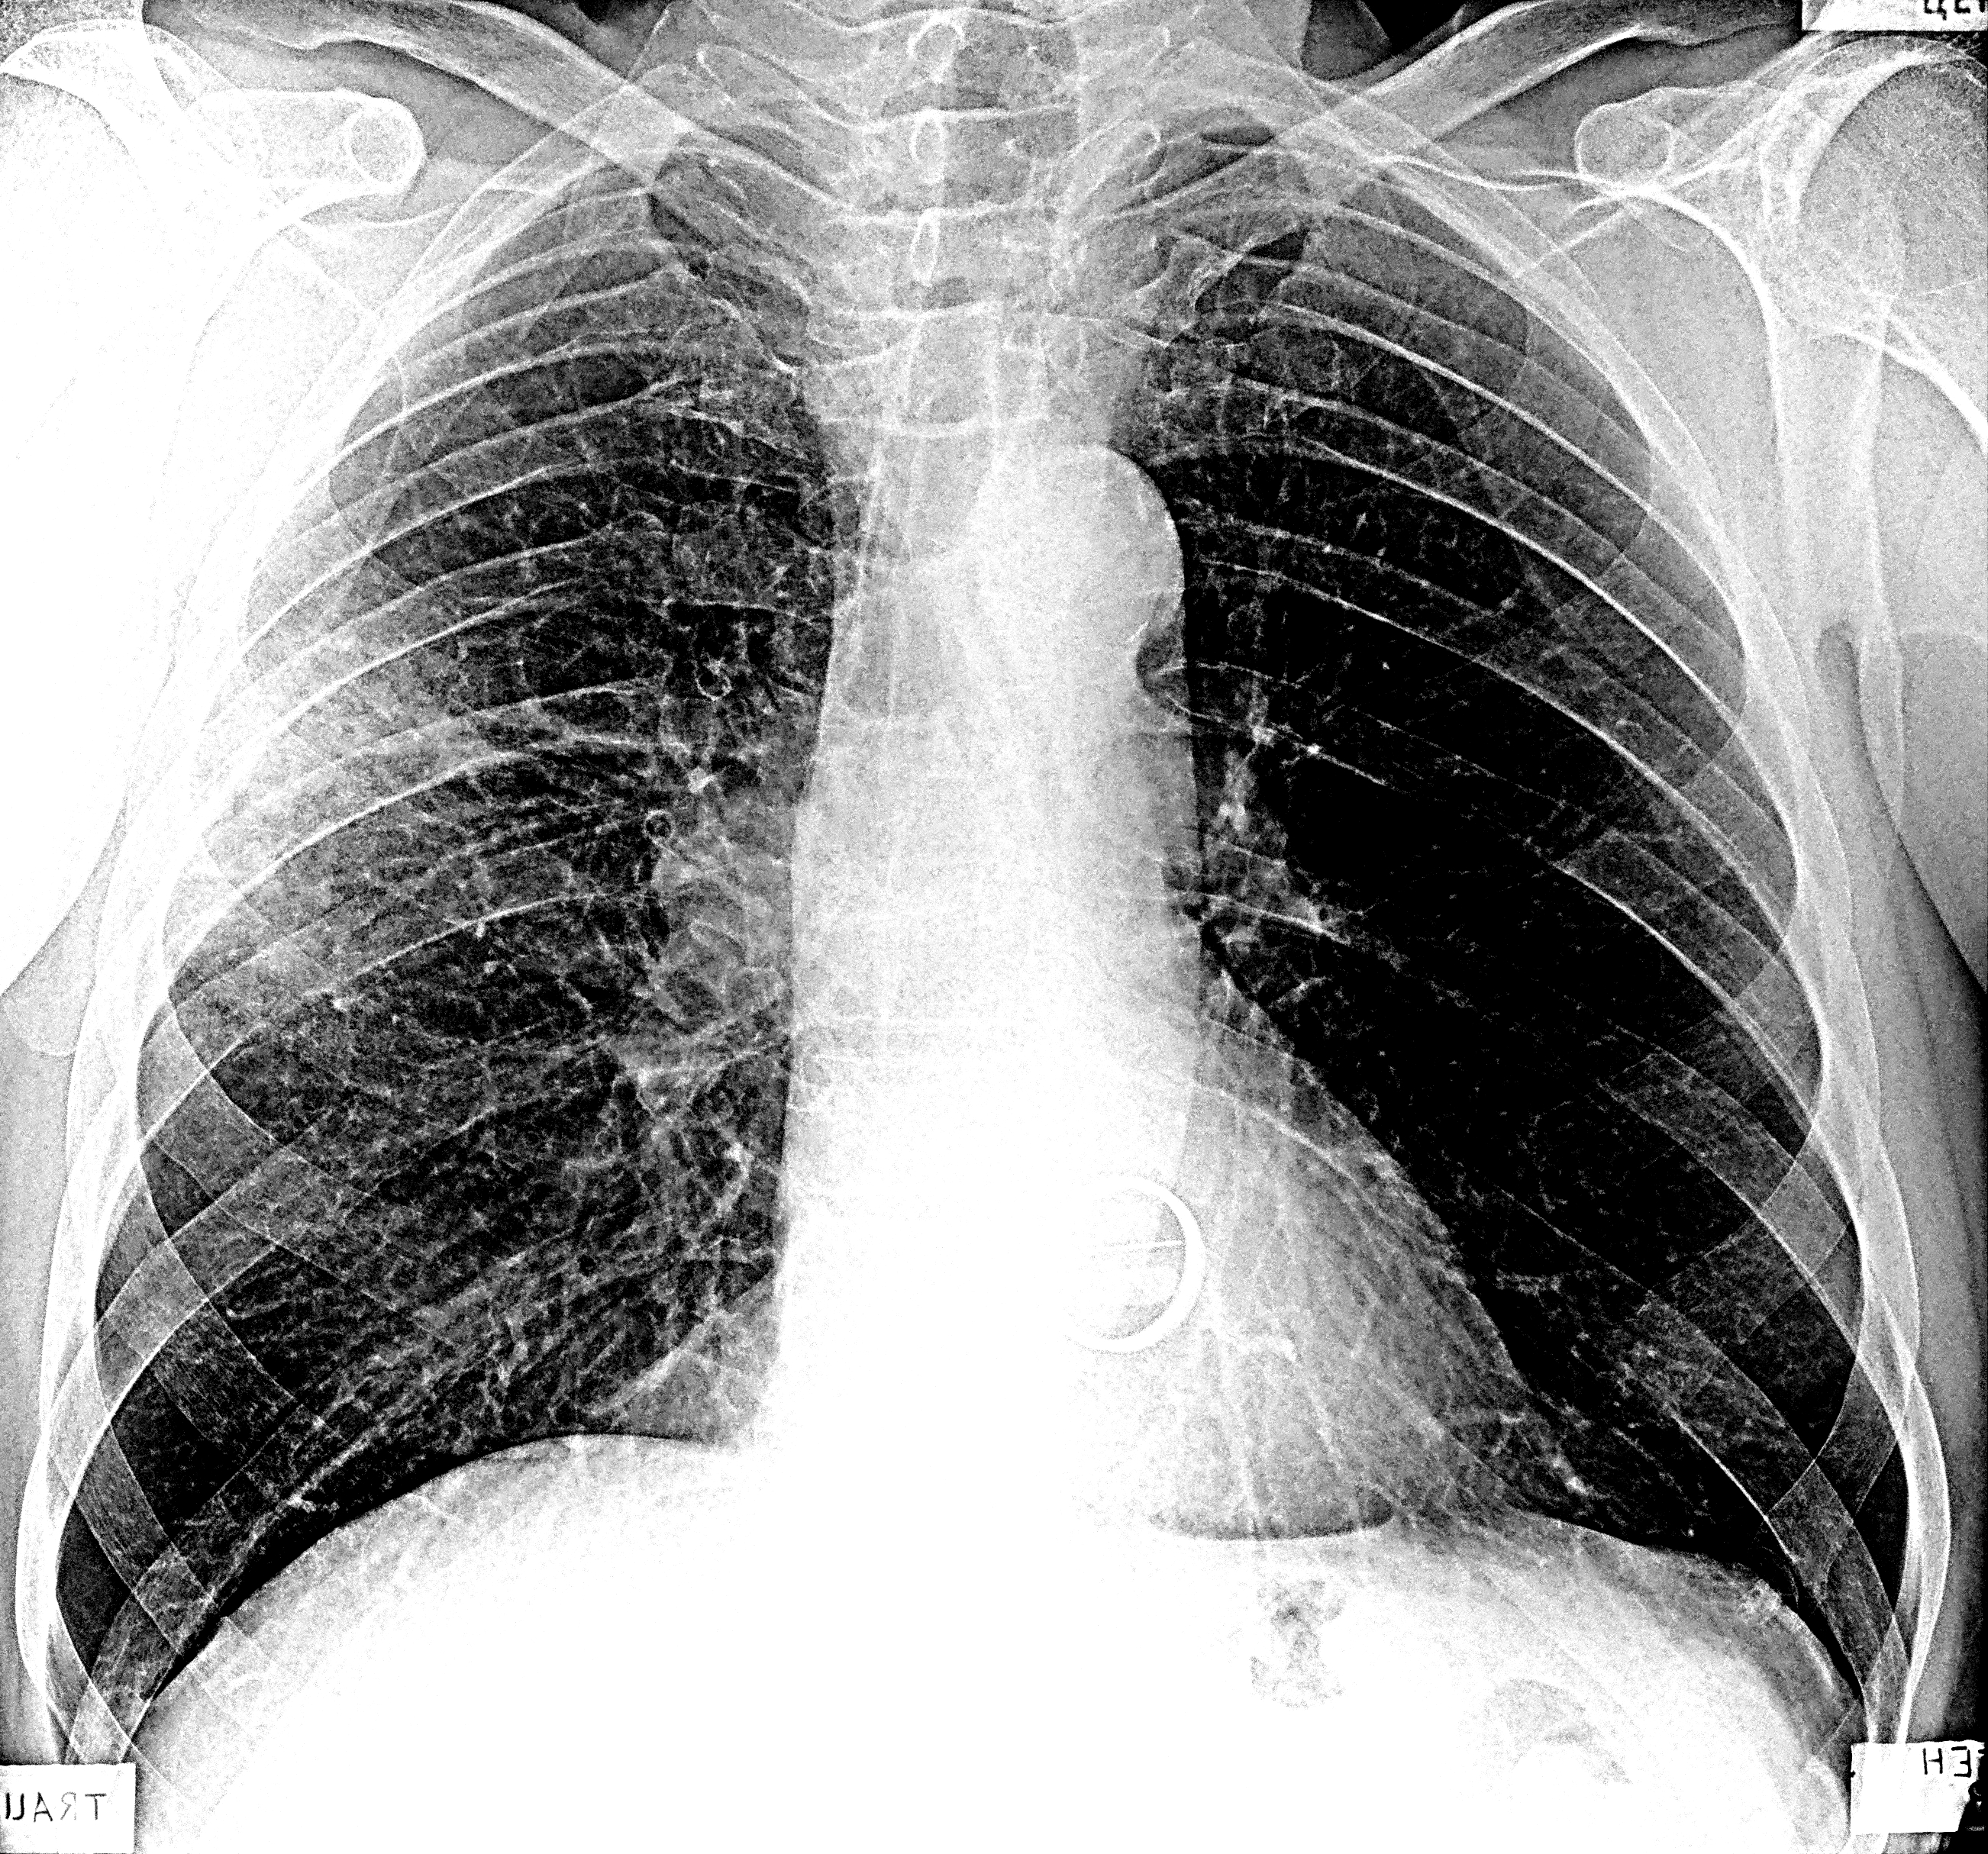

Поражение легких является одним из основных симптомов коронавируса (COVID-19). В данной статье представлены фото рентгеновских снимков, которые позволяют визуально оценить состояние легких при этом заболевании.

На фотографиях рентгеновских снимков видно, как вирус воздействует на легочную ткань. Характерные признаки поражения легких включают пятна, инфильтраты и наличие жидкости внутри легочных альвеол.

Фото рентгеновских снимков помогают врачам и специалистам визуально определить степень поражения легких и принять соответствующие меры лечения и поддержки пациента.